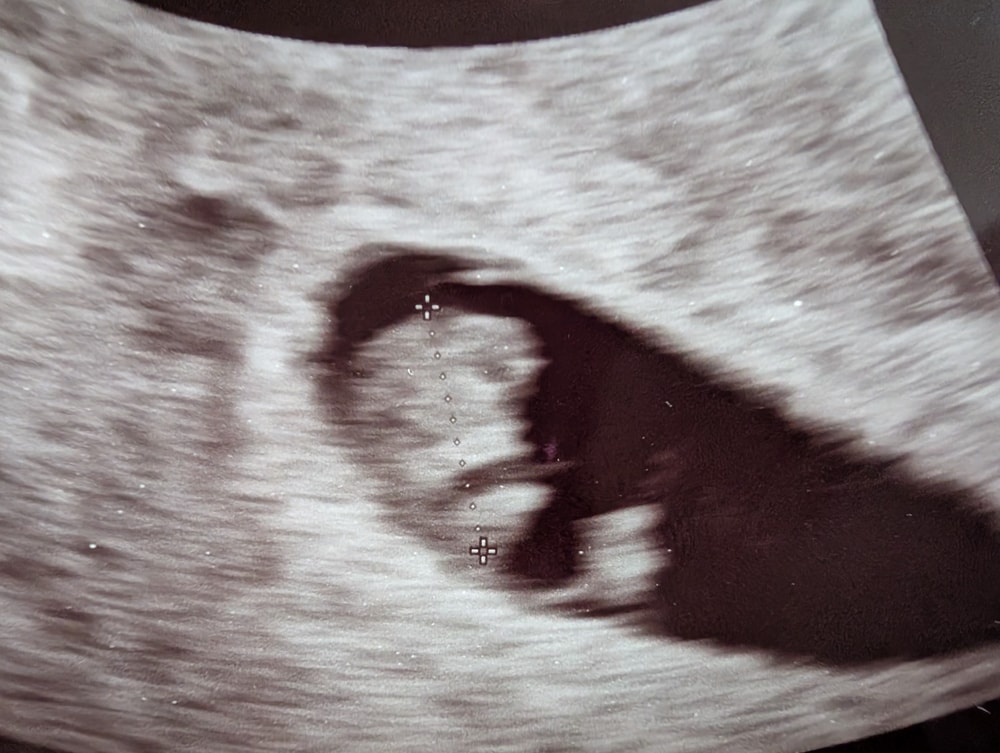

На УЗИ ходили с мужем (он со мной 3 раза рожал, трансвагинальное узи его не пугает), все замерили, показали сердечко.

Все четко ТТТ по срокам 🤗 Креветочка растёт, уже виден глазик, ручки, ножки крошечные, почти как на картинке в приложении 🤗 Муж даже всплакнул от умиления 🙂↕️